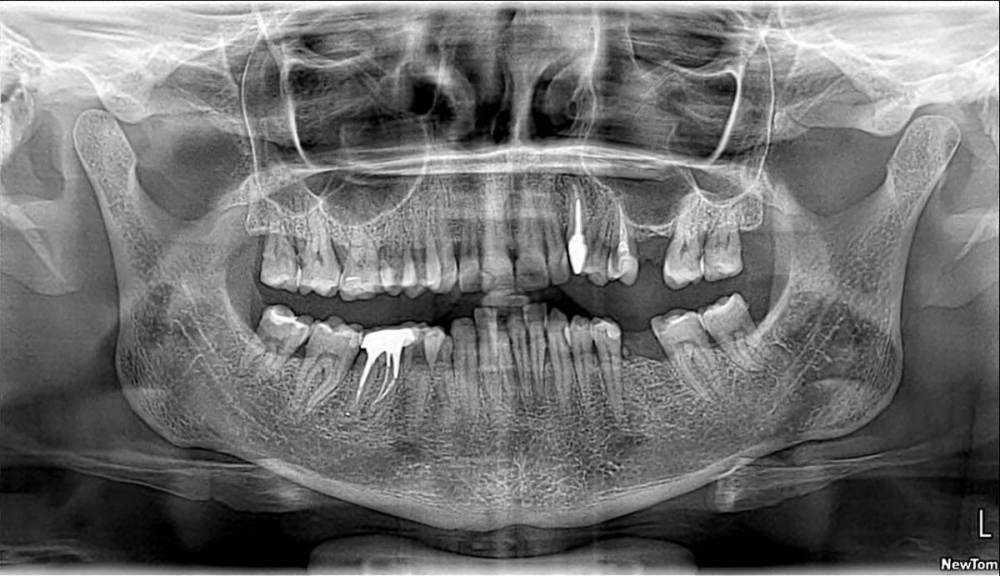

Jyuly Опубликовано 30 мая, 2023 Поделиться Опубликовано 30 мая, 2023 Добрый день! 4 года назад установила керамическую вкладку E-MAX на "живой" зуб (предлагали на выбор пломбу или вкладку, как более долговечный и надежный вариант). 4 месяца назад вкладка начала "гулять", терапевт осмотрел, сказал, что она треснула + кусочек небольшой откололся. Была у ортопеда в марте, он сказал после осмотра и свежей ортопанорамы от февраля этого года (свежего прицела не было) что, велика вероятность, зуб придется депульпировать. Скажите, пожалуйста, можно ли по снимку сказать (одному из них 2 года, другому точно не знаю, ~3-4) степень вероятности депульпирования зуба? Что это за "шарик" внутри? Несколько дней, как зуб начал беспокоить, точнее, не сам зуб, а выше, челюсть ноет, отдает в область глаза и уха. Может, это и не от этого зуба боли, между 7 и 8 кариес по снимкам. Хороший терпевт, которого мне посоветовали, в отпуске до 29 июня, я и не понимаю, какого специалиста мне искать спешно - терапевта, для пломбирования каналов или ортопеда для установки новой вкладки. Помогите, пожалуйста, просто крик души! Москва Ссылка на комментарий

Carioznik Опубликовано 31 мая, 2023 Поделиться Опубликовано 31 мая, 2023 (изменено) 22 часа назад, Jyuly сказал: можно ли по снимку сказать (одному из них 2 года, другому точно не знаю, ~3-4) степень вероятности депульпирования зуба? Нет 22 часа назад, Jyuly сказал: какого специалиста мне искать спешно - терапевта, для пломбирования каналов или ортопеда для установки новой вкладки Думаю, нужно начать с ортопеда, чтобы он определил план действий по этому зубу. (либо будет делать сам , либо к терапевту сначала отправит) Изменено 31 мая, 2023 пользователем Carioznik 1 Ссылка на комментарий

Carioznik Опубликовано 2 июня, 2023 Поделиться Опубликовано 2 июня, 2023 2 часа назад, Jyuly сказал: что это за шарик может быть? Дентикль 1 1 Ссылка на комментарий